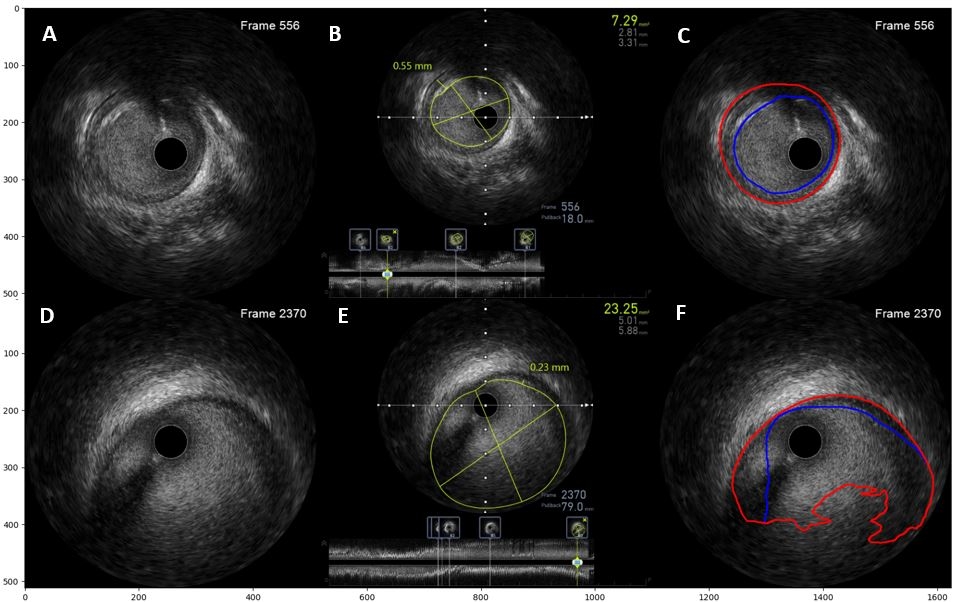

Results: In 163/706 frames (23.1%), DeepIVUS labeling resulted in segments with jagged or non-physiologic shapes. These were automatically discarded using a quantitative ovalness criteria, Figure 1. Agreement between DeepIVUS predicted MIT and expert measured MIT in the remaining 543 frames yielded a strong Pearson correlation coefficient of 0.81 with an R2 of 0.65, Figure 2A. The linear fit was used to determine the DeepIVUS IT cutoff (0.554mm) which corresponded to clinical cutoff of 0.5mm. Using this value, DeepIVUS correctly classified 86.6% of frames (sensitivity 85.1%, specificity 87.9%, aF1 0.86), Figure 2B.